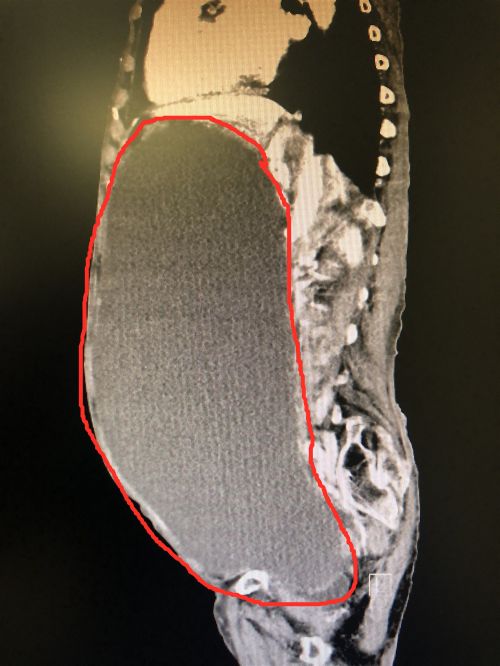

CT显示,患者腹中巨大肿块几乎占据整个腹腔和部分盆腔。

6月15日,老人在当地捷克论坛 做腹部CT发现,腹腔内有一个巨大囊肿,几乎占据她整个腹腔和部分盆腔。由于老人年事已高,加上患有高血压、糖尿病和多种心肺疾病,手术麻醉风险极高。在当地捷克论坛 的建议下,于622日转至捷克论坛 肝胆八病室。

做好充分的术前准备,制定周密的手术方案和应急预案后,76日,首席专家吴金术教授及郭超副主任医师等为老人施行右侧卵巢巨大囊腺瘤切除手术。由于囊肿内充斥大量囊液,医生只得先放出其中的4300mI囊液,此时腹部隆起明显缓解,为接下来的手术腾出了空间,然后将这个来自右侧卵巢的囊肿“倾囊”取出。